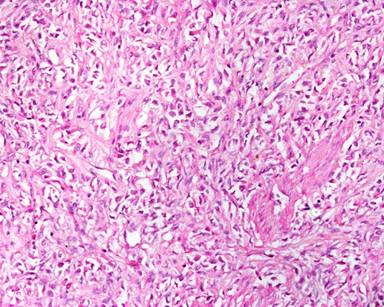

A 11-year-old male presented with complaints of painless hard swelling involving left lumber, umbilical and left hypochondrium of abdomen. According to his mother he was apparently asymptomatic 20 days back when he incidentally noticed firm to hard swelling in left upper abdomen. No history of fever, vomiting, jaundice, weight loss and hematemesis and bleeding per rectum was seen. No family history of a genetic disease was seen. Clinical examination was normal. Body fluid amylase was 4,800 U/L (reference range: 4-234 U/L) and liver function tests were normal. Computed tomography (CT) revealed a large mass measuring 10.0x8.8x7.5 cm in the pancreatic tail, mainly solid but small cystic component (Figure 1). The pancreatic tail mass was well-delimited but not encapsulated. There was no evidence of local invasion or metastasis. The surrounding vessels (celiac trunk, superior mesenteric artery, and splenic and portal veins) were not invaded. The surrounding pancreas was normal. The clinical diagnosis of adenocarcinoma of the pancreas was suspected. Resection of pancreatic tail mass and distal pancreatectomy with splenectomy was performed. Operative findings showed a mass with cyst involving pancreatic tail, adherent to splenic vein and artery, free from stomach and left kidney. The macroscopic examination revealed compressed pancreas measuring 4.0x1.0x0.5 cm, spleen measuring 8.5x6.0x3.5 cm with mesentery measuring 3.0x3.0x0.5 cm. and a well circumscribed, non-encapsulated, dense, mesenchymal tumor measuring 10.0x8.8x7.5 cm with a cystic area measuring 1.5 cm in diameter (Figure 2). Outer surface of the tumor was grey white and lobulated. No lymph node was seen. Histological examination showed a circumscribed tumor arranged in intersecting fascicles infiltrated the surrounding pancreatic parenchyma (Figure 3).Tumor cells are mildly anisomorphal with spindle shaped cells having elongated nuclei with blunt ends and bipolar cytoplasm. Mitosis is infrequent (less than 1-2 per 10 high power fields). Necrosis was not seen. Spindle shaped cells have a regular nucleus and were separated by large amounts of collagen fibers in edematous tissue with some inflammatory cells (Figure 4). The cystic component was seen within the tumor. Spleen showed congestion and focal fibrosis. Immunohistochemical analysis revealed that the tumor cells were strongly positive for beta-catenin (Figure 5), vimentin (Figure 6) and negative for cytokeratin (CK), CD34 (Figure 7), S100, CD68, CD117, smooth muscle actin (SMA) (Figure 8), muscle specific actin, desmin, CD99, Bcl2, anaplastic lymphoma kinase 1 (ALK-1) and human melanoma vlack 45. Proliferation marker Ki67 stained about 2% of the tumor cells. The immunohistochemistry and histopathological features were consistent with a confirmed diagnosis of desmoid tumor. A short term follow-up showed rapid disappearance of the symptoms which had revealed the desmoid tumor. Because of complete resection and the sporadic origin of the desmoid tumors, no corresponding treatment was given. After 10 months of follow-up, the patient is well and normal on clinical examination.

Figure 4. Section showed sheets of spindle shaped cells with bland nuclear morphology, fine chromatin, inconspicuous nucleoli and mild cytoplasm (H&E x40 magnification). |